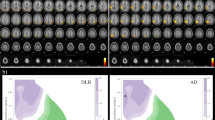

Creation of a prototype ROI map

First, stereotactic anatomical standardization was performed. The original FDG-PET image data were transformed into a binary format. They were transformed into a standard Talairach space using the NEUROSTAT program [6], which contains all three-dimensional stereotactic surface projection (3D-SSP) programs (Dr. Minoshima, Department of Radiology and Bioengineering, University of Washington, Seattle, USA). Differences in size between the individual brain and the standard template were removed by linear scaling. Regional anatomical differences between the individual and the standard template were minimized by automated non-linear warping. Next, peak cortical activity in the brain was subjected to a three-dimensional search with a predefined vector for each stereotactic surface pixel after anatomical standardization. The peak value was projected back and assigned to the originating surface pixel. This procedure was continued on a pixel-by-pixel basis covering the whole cortex of the brain. Pixel values of an individual’s image set were normalized to the whole brain, the thalamus, the pons, the cerebellum and the sensorimotor value with the 3D-SSP program in NEUROSTAT [6]. The sensorimotor cortices were defined as reference regions for normalization [9, 10]. Pixels with significantly decreased metabolism in the DLB group (p < 0.05), which were obtained from a comparison between the AD group and the DLB group (the first group), were plotted as a prototype DLB ROI map (Fig. 1). The AD group had no regions with significantly lower metabolism compared with the DLB group (the first group).

Representative cases

Figure 3 shows the conventional FDG-PET images (a) and Z score map (b) of a 74-year-old male patient with DLB. His MMSE score was 26. All the observers could easily diagnose this case as DLB by visual inspection of the conventional FDG-PET images because of a typical metabolic reduction pattern. The automatic diagnosis system also diagnosed it as DLB. Figure 4 shows the conventional FDG-PET images (a) and Z score map (b) of a 71-year-old female with AD. All the observers and the automatic system could diagnose this case as AD. Figure 5 shows the findings in a 74-year-old male DLB patient with an MMSE score of 21; two experts and one beginner diagnosed this case as DLB, while the other expert considered it equivocal and the other beginner diagnosed it as AD. The automatic diagnosis system could not diagnose this case as DLB.